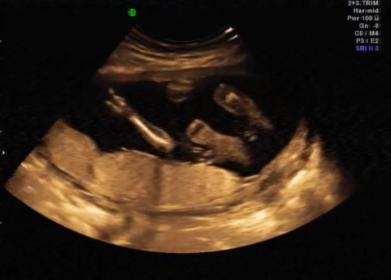

Guesses? 18 week 3D sonogram Video

I'm sooooo excited to know the gender but my husband doesn't want to find out so I'm hoping the experts here can please give me an answer :-)

Here's an image

p.s - if you spot any girly/boy parts please let me know what minute/sec...i'd love to see for myself too

Attachment 3290